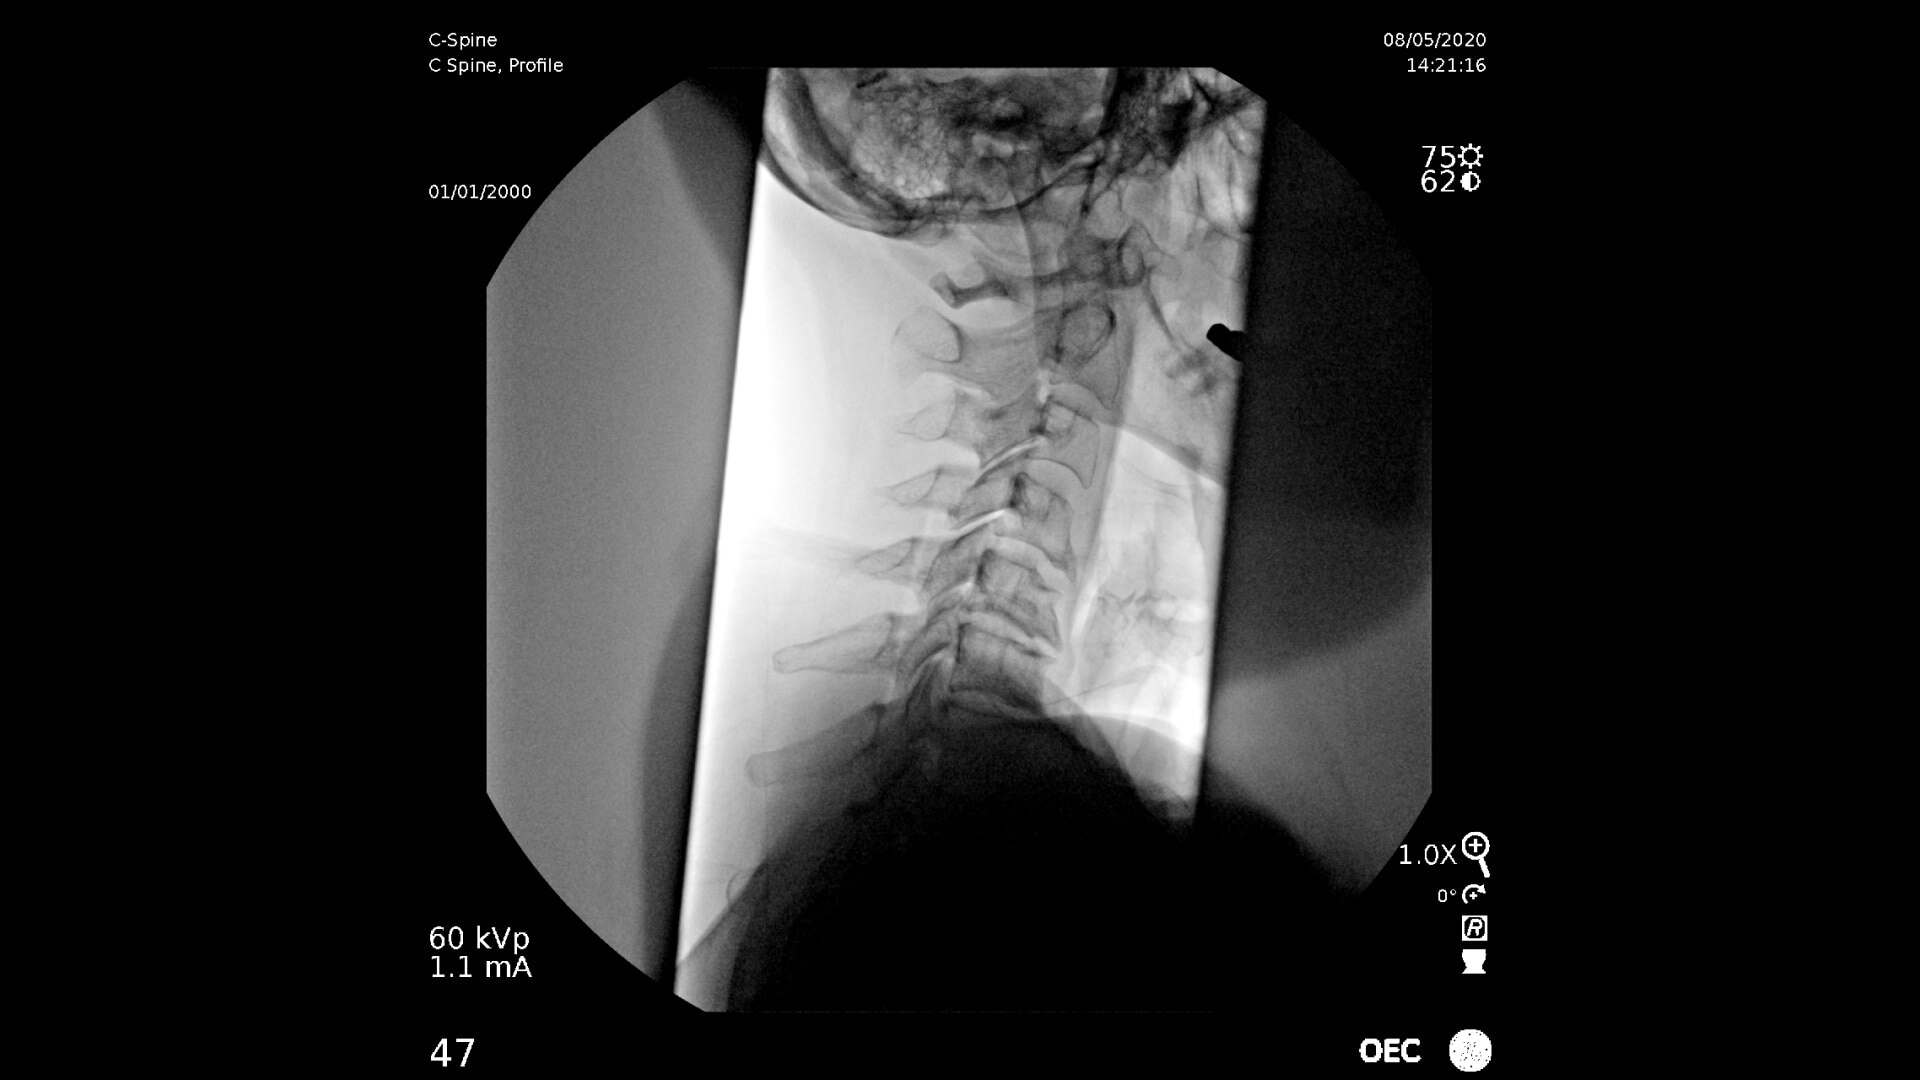

C-arms for Pain Management

Consistently experience amazing image quality, precision, and efficiency during simple to complex pain management procedures with OEC C-arms.

Achieve precision and efficiency while experiencing the image quality needed during simple to complex pain management procedures with OEC C-arms.

See clear detail captured on a flat panel detector to a 4K display for visualization of anatomical detail.

Live Zoom up to 4Xs to see needle placement, without the use of Mag mode. Live Zoom also enable panning to an area of interest without having to move the base of the C-arm.

Pain management imaging you need

Pain Management procedures require powerful imaging systems.

OEC C-arms perform imaging in a variety of procedures such as:

• Cervical spine pain management